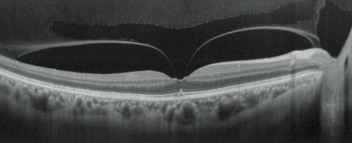

高清追蹤plus功能

高清追蹤plus功能可追蹤無意識的眼球運動,在SLO圖像上保持相同的掃描位置,確保精確的圖像采集。此功能可獲得多至120張疊加的高清圖像。